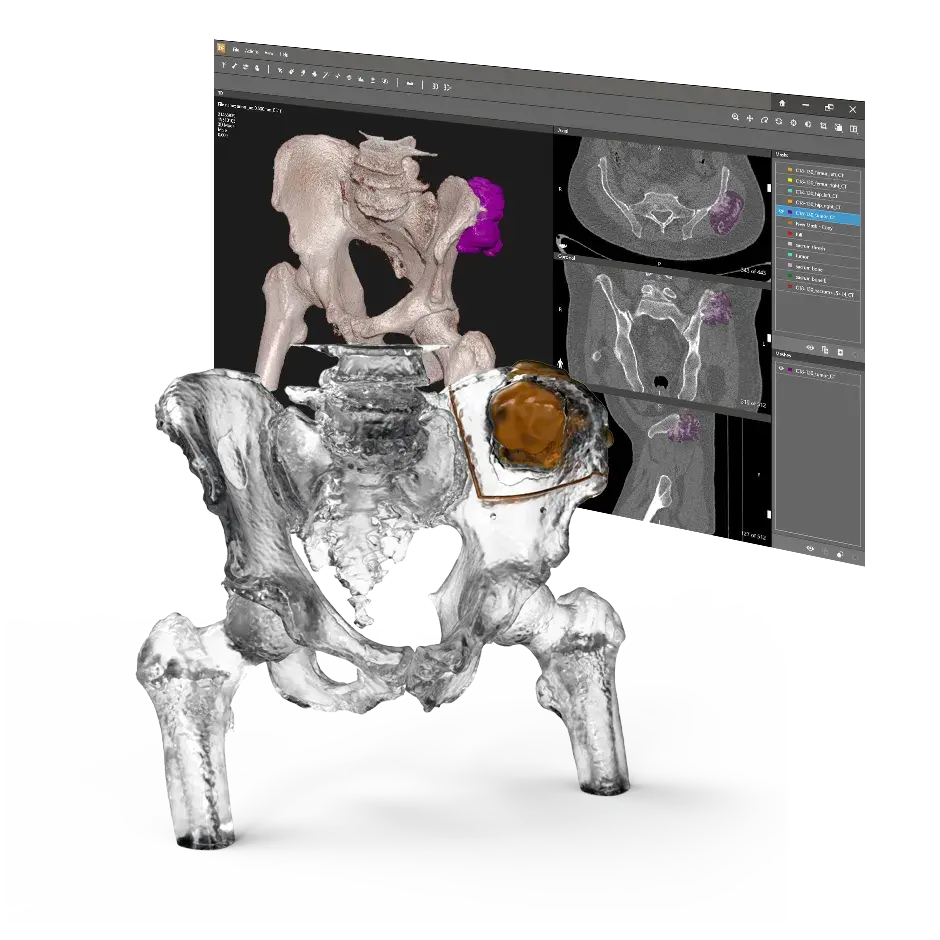

3D Systems' VSP® surgical planning solutions for craniomaxillofacial (CMF) applications received FDA clearance as a service-based approach to personalized surgery over 10 years ago.

3D Systems and Stryker Corporation have partnered to provide surgeons with best-in-class products and services for craniomaxillofacial surgeries. As a leader in personalized healthcare solutions, 3D Systems has planned and delivered devices for more than 140,000 patient-specific cases. The Stryker Craniomaxillofacial business specializes in providing patient-specific options and innovative solutions that help drive efficiencies in surgical suites. The combination of Stryker’s specialized team and advanced implants with 3D Systems' cutting-edge 3D printing technologies and expert consulting services positions both companies to provide a superior level of service to healthcare professionals who use these revolutionary solutions.